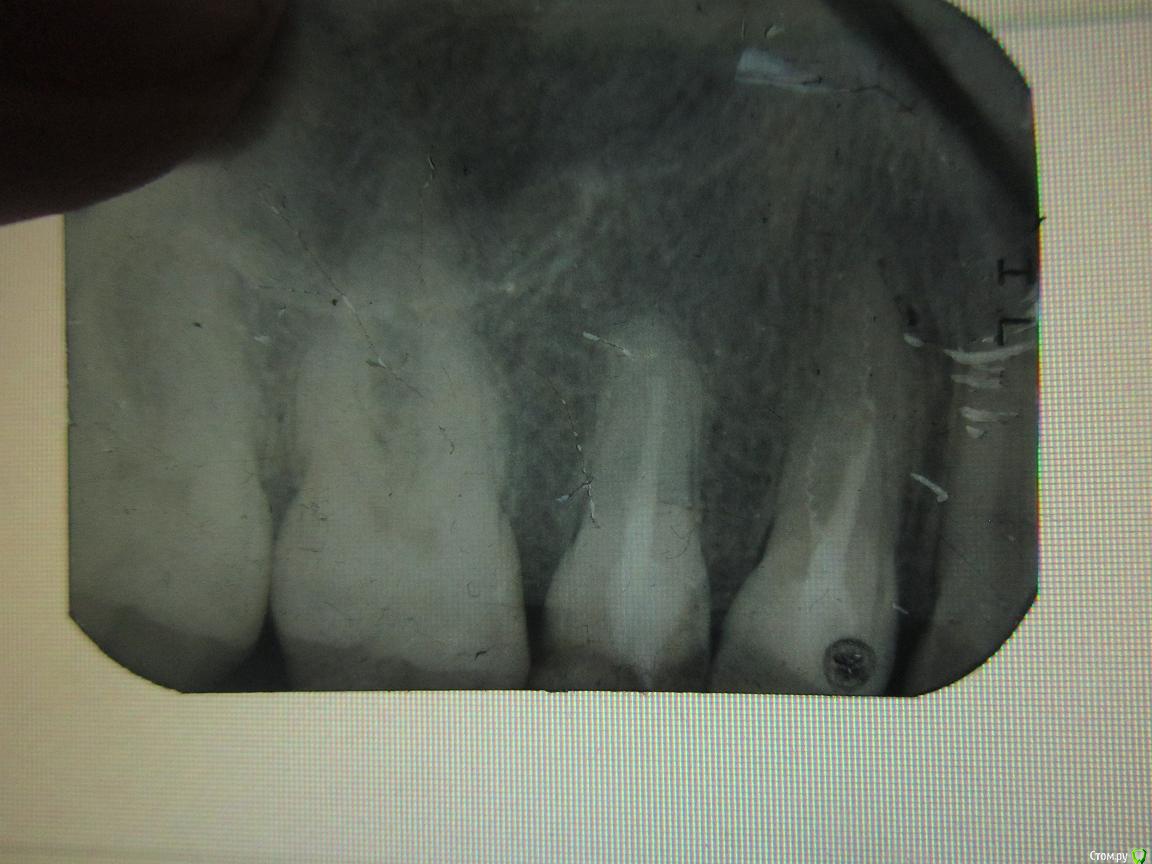

мухит Опубликовано 2 июня, 2015 Поделиться Опубликовано 2 июня, 2015 (изменено) Пломбировал два зуба с разницей в год ,( один месяц назад) Зуб начал беспокоить , пошел к другому стамотологу , он сказал надо удалять два зуба т.к воспаление корня. Действительно ли нет выхода или стоит обратиться в область? На фото 2 зуба справа ( а так они 14 .15). Второй стоматолог сказал что зубы вылечены не до конца. И второй вопрос у меня уже 5 кариес за два месяца. Связано ли это что я пол года назад переехал в другую страну? Изменено 2 июня, 2015 пользователем мухит Ссылка на комментарий

мухит Опубликовано 3 июня, 2015 Автор Поделиться Опубликовано 3 июня, 2015 Удалять не нужно. Нужен грамотный терапевт с микроскопом и тогда есть хорошие шансы на излечение обоих зубов + 1 перелечить и протезировать нет, скорее всего проглядели Каналонаполнители.Не вижу проблемы. Спасибо всем, а вот там на снимке на одном из зубов какая то спираль, она там не будет гнить? Ссылка на комментарий

anvladd Опубликовано 3 июня, 2015 Поделиться Опубликовано 3 июня, 2015 Это каналонаполнитель и его нужно и можно вытащить. 1 Ссылка на комментарий